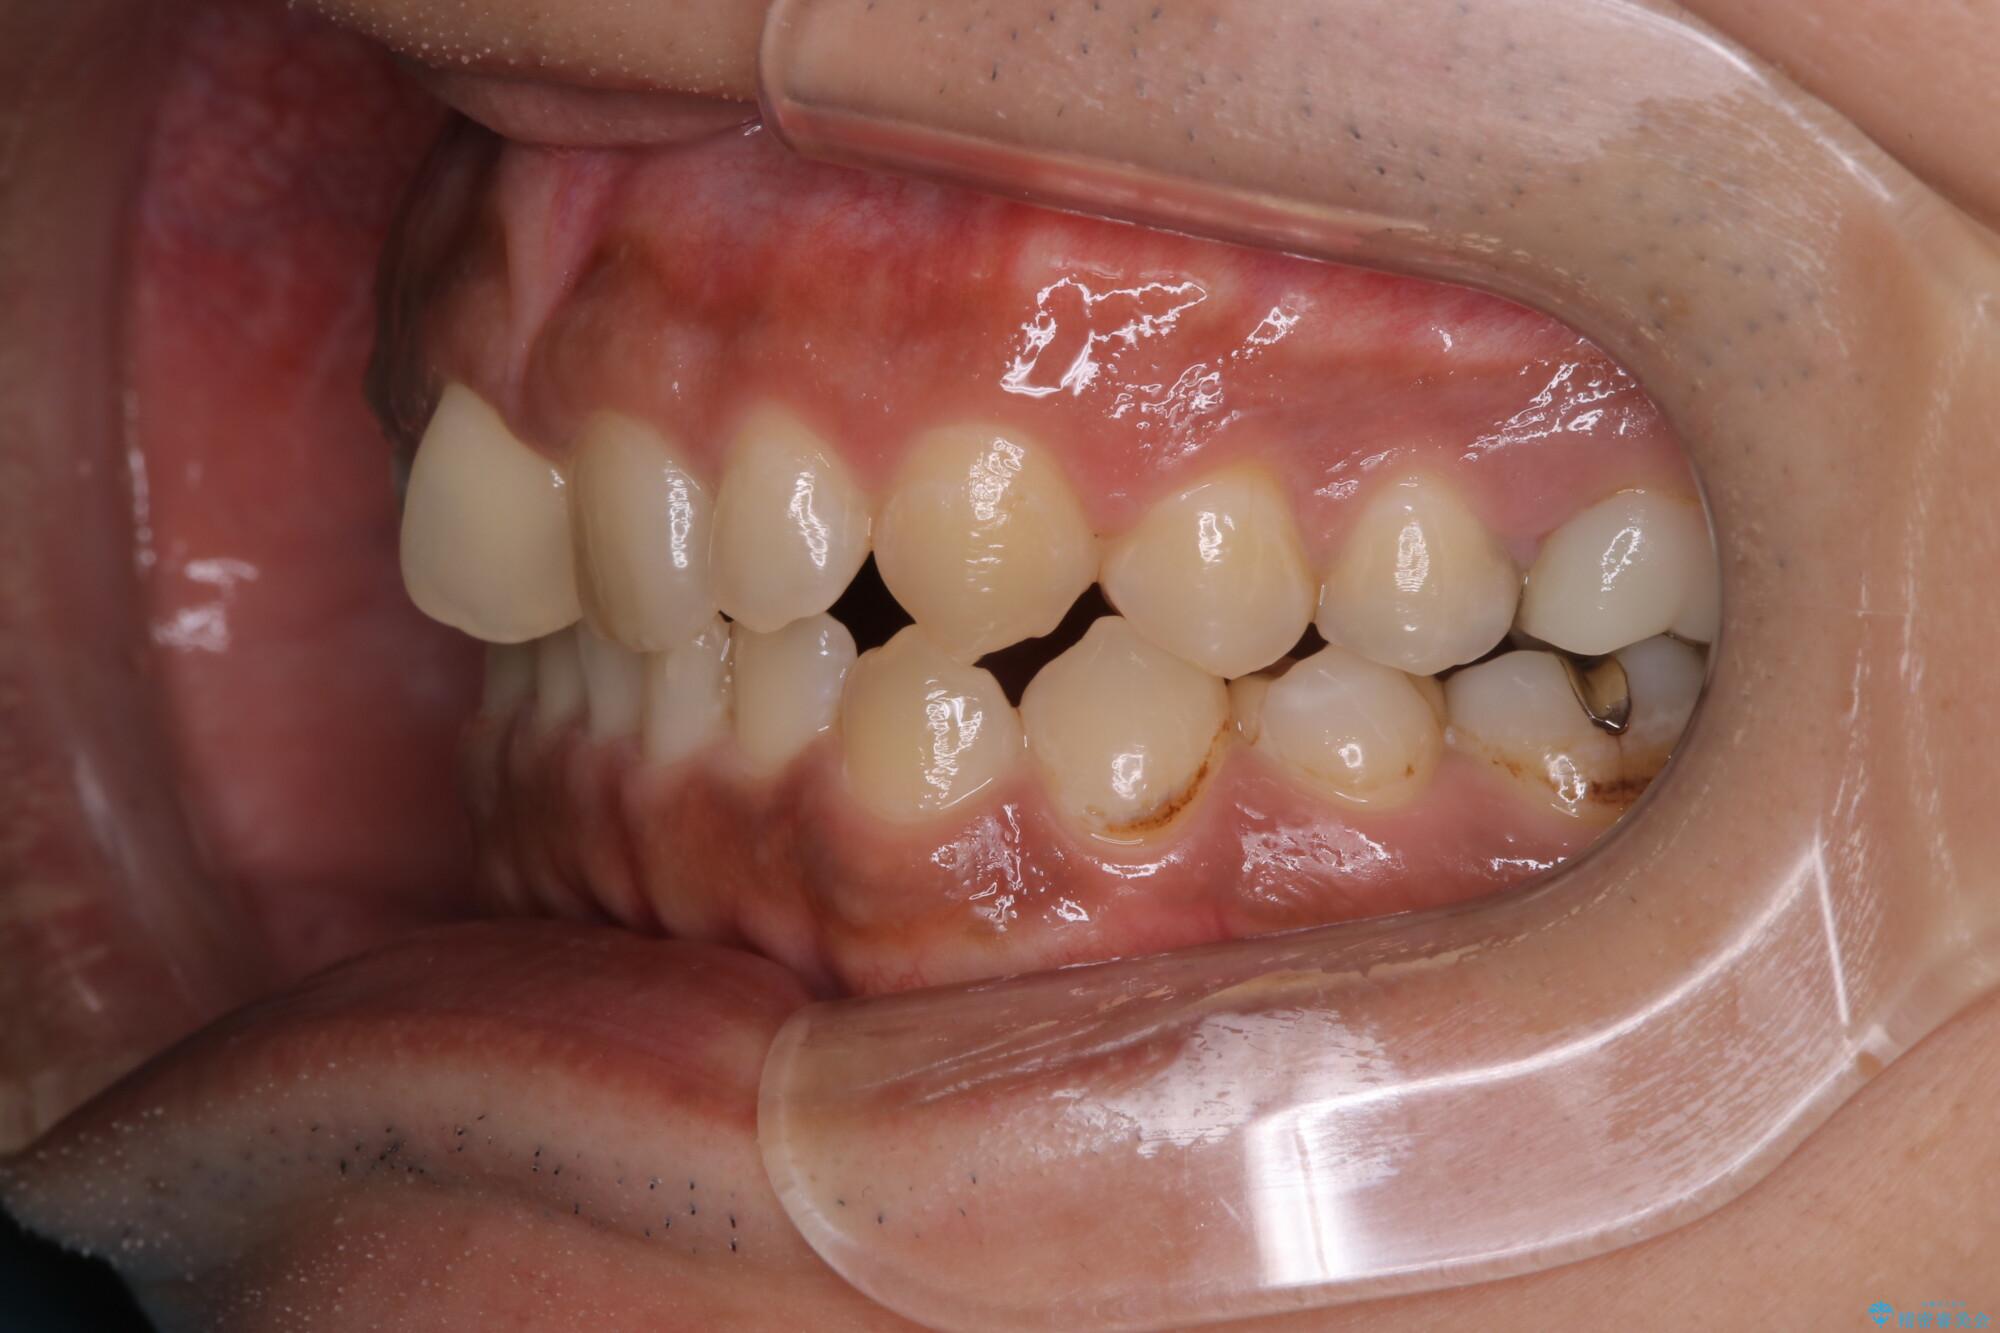

【モニター】インビザライン 前歯の捻れを治したい

- 30代男性

- 矯正装置

- インビザライン

- 治療期間

- 1年6ヶ月

- 治療計画

- 上下の前歯のがたつきを主訴に来院されました。インビザラインで治療可能と判断致しましたので、IPR(歯と歯の間を削る処置)と歯列弓拡大をして

がたつきをとる治療計画を立てました。

マウスピースをしっかり使用していただいたことで、主訴である前歯のがたつきも改善され

リファイメントも1回のみで治療を終了することが出来ました。